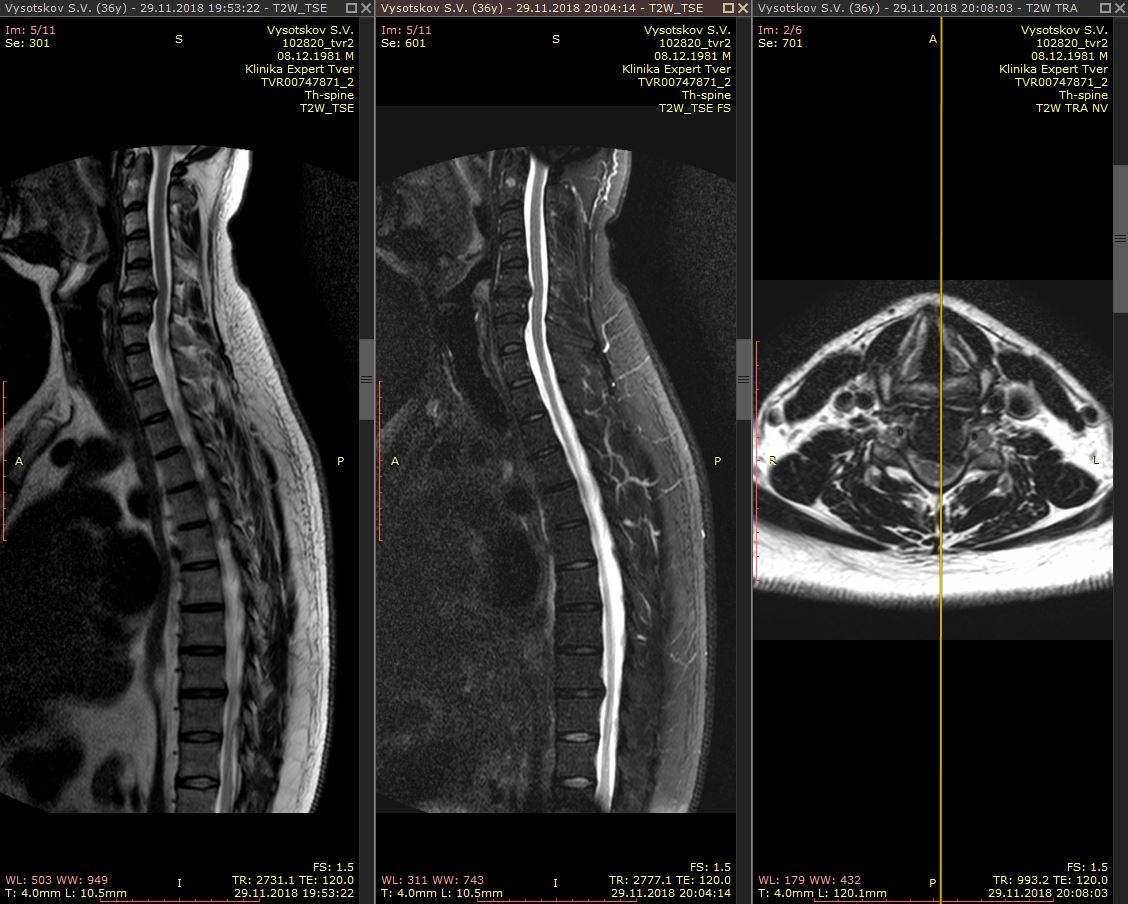

Рис - МРТ грыжи шейного отдела позвоночника